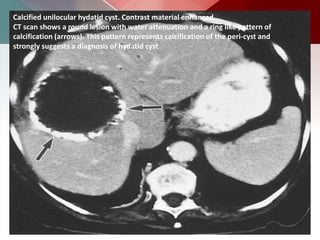

Calcified unilocular hydatid cyst. Contrast material enhanced

CT scan shows a round lesion with water attenuation and a ring like pattern of

calcification (arrows). This pattern represents calcification of the peri-cyst and

strongly suggests a diagnosis of hydatid cyst